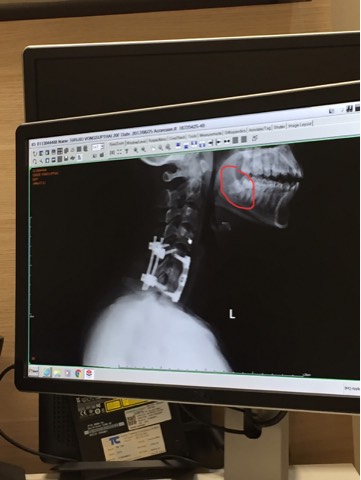

ฟันคุดลักษณะแบบนี้มีความจำเป็นต้องผ่ามากขนาดไหนคะ

เราไป x-ray ที่ผ่าตัดคอมา แต่แอบเห็นฟันกรามว่าฟันมันเอียงๆ เลยคิดว่าน่าจะเป็นฟันคุดจากที่เทียบรูปดูทางเน็ต ตอนนี้เราไม่มีอาการเจ็บปวดอะไรค่ะ

อยากทราบว่าถ้าใช่ฟันคุดเรามีความจำเป็นมากน้อยแค่ไหนที่จะต้องรีบไปผ่าคะ ถามพี่สะใภ้เค้าเคยผ่าฟันคุดมาก่อน เค้าบอกว่าถ้าไม่ปวดก็ไม่จำเป็นต้องผ่า เลยอยากถามผู้รู้ให้แน่ใจค่ะ